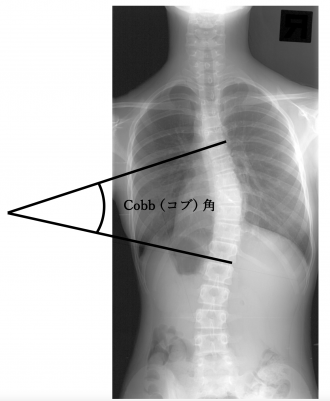

第1回 脊柱側弯症について脊椎手術.com。